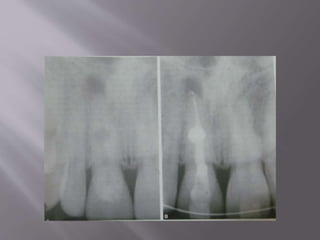

 Pressure resorption due

to orthodontic

treatment. A. Teeth at

the start of orthodontic

treatment. B. Severe

root resorption on the

left central incisor after

orthodontic treatment.

Note that, even though

considerable resorption

has taken place,

favorable healing at the

apex with cementum

can be seen. (Courtesy

Dr IB Bender)